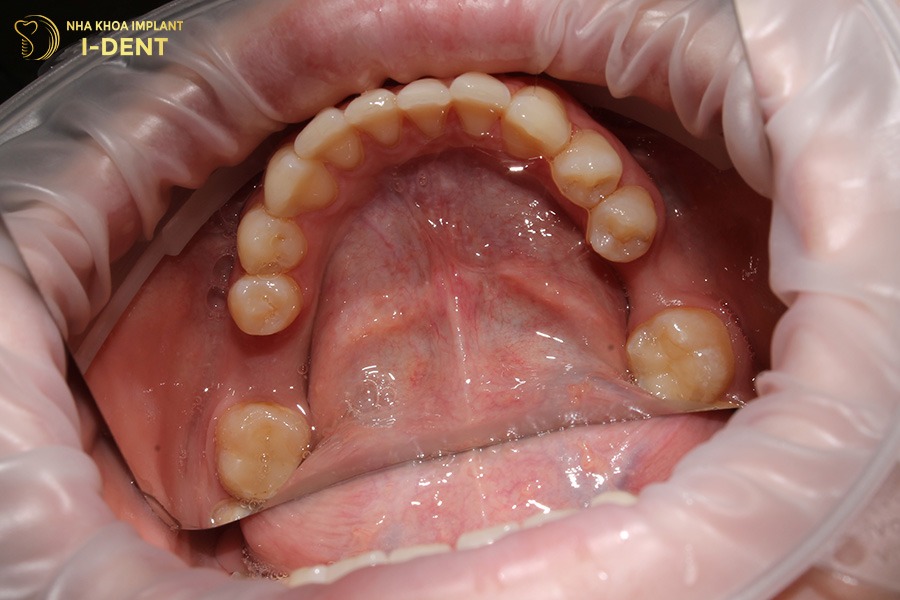

2.1. Xương tại vị trí mất răng bị thu hẹp về kích thước và chiều cao

Sau khi mất răng, phần xương ổ răng tại vị trí đó không còn nhận được lực nhai tự nhiên khiến xương bắt đầu tiêu dần theo thời gian. Thời gian đầu khi bị mất 1 hoặc nhiều răng mà chưa kịp trồng lại răng mới thì khi há miệng và soi gương sẽ thấy xương của vùng mất răng (vẫn đang được bao phủ bởi mô lợi) đang bị thu hẹp về chiều cao và hoặc chiều trong ngoài.

Tuy nhiên, nếu một thời gian dài không can thiệp thì tình trạng xương bị tiêu nặng, lúc này sẽ thấy một gờ xương nhô cao ở giữa vùng sống hàm, phía phía bên trong và bên ngoài thấp hơn. Còn theo chiều trên dưới, sẽ thấy vùng xương mất răng bị thấp xuống tạo thành mọt lõm trũng sâu so với các vùng xương kế cận.

Những thay đổi này là dấu hiệu cảnh báo tiêu xương răng đang diễn tiến nghiêm trọng. Nếu không được thăm khám và can thiệp kịp thời, phần xương có thể tiêu đến mức không đủ thể tích để trồng răng mới.

Sau khi mất răng, vùng xương ổ răng dần thu hẹp và lõm sâu.